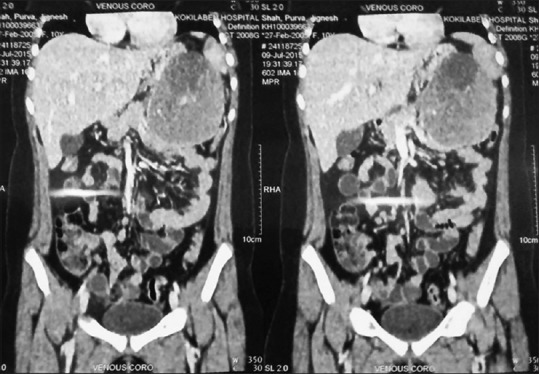

An ultrasound of the abdomen revealed a large mass in the lesser sac. A computed tomography scan of the abdomen showed a large heterogeneous mass, partly solid, and partly cystic in nature occupying the entire lesser sac abutting the pancreas and the spleen [Figure 1]. The left kidney and the stomach were in proximity but not affected. The mass showed a well-defined margin, but the organ of origin could not be conclusively determined.

| Figure 1:Computed tomography scan of the abdomen showing a large heterogeneous mass, partly solid, and partly cystic in nature occupying the entire lesser sac abutting the pancreas and the spleen